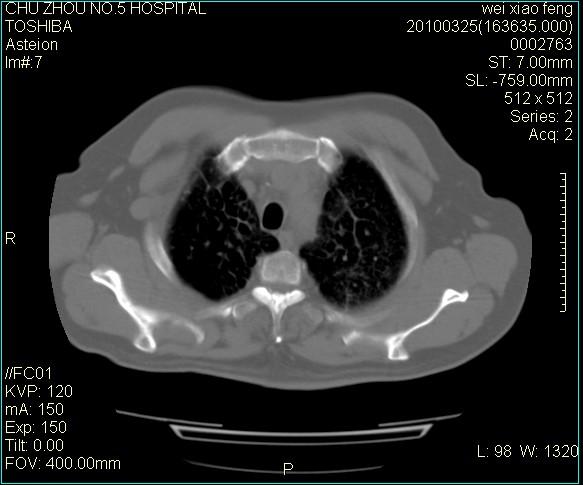

男,60岁,反复咳、痰、喘3月,加重3天。

双肺间质性改变。

考虑双肺血型潘散肺结核/

间质性肺炎伴间质纤维化!不排除伴有职业病!

急性血型潘散肺结核。

双肺间质纤维化,双肺血型潘散肺结核。

考虑间质性肺炎伴间质纤维化。

右肺中叶结节影为原发灶,考虑右肺中叶周围型肺癌并淋巴道转移